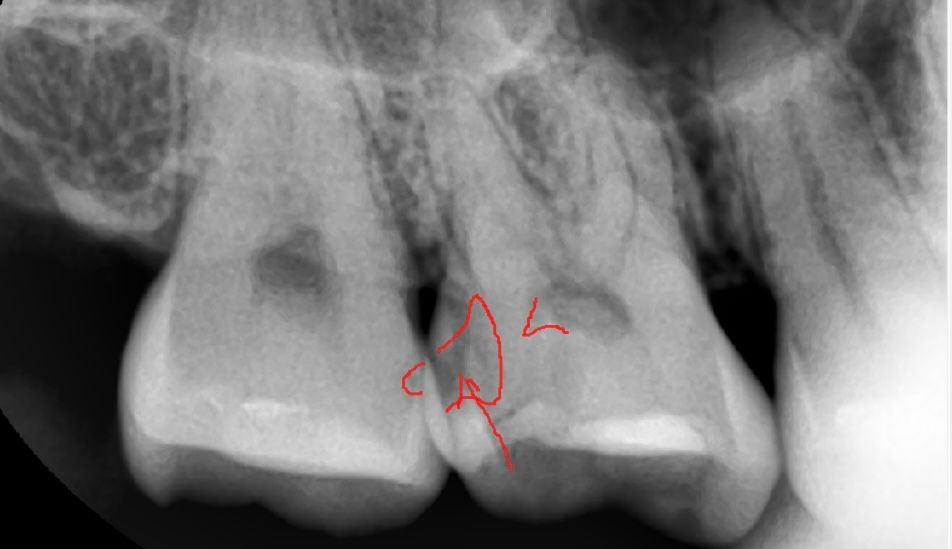

사진은 오늘 제가 신경치료 받은 치아입니다...

• 1번 째 사진